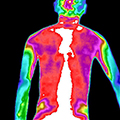

治疗前后炎症对比图/ Inflammation contrast

• 治疗后